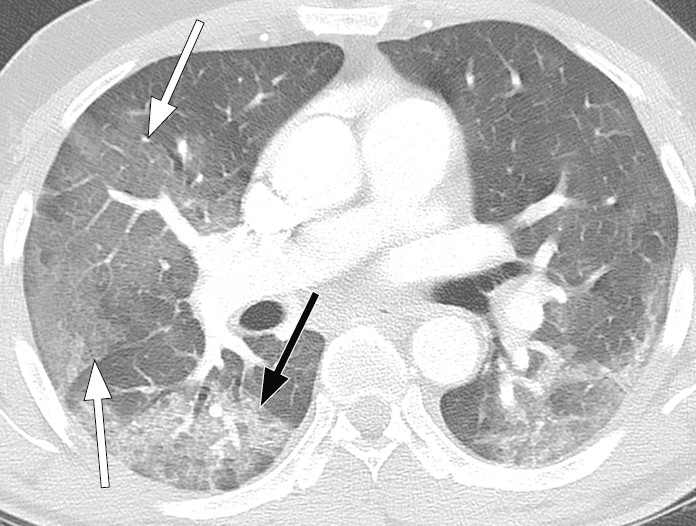

Typiske CT-funn varierer med symptomvarighet og kan deles i tre stadier: en tidlig fase, en intermediær fase som strekker seg fra 3–5 dager etter symptomdebut, og en senfase. Det er ikke alltid funn på CT de første dagene etter symptomdebut. I et materiale med symptomatiske, men uspesifiserte pasienter hadde 56 % normale funn på CT innen to dager etter symptomdebut (12), avtakende til 9 % 3–5 dager etter symptomdebut og 4 % 6–12 dager etter symptomdebut. Funnhyppighet varierer med sykdommens alvorlighetsgrad. Ved første gangs bildediagnostikk var det normale funn hos 18 % i en gruppe pasienter med ikke alvorlig sykdom, men hos bare 3 % av pasienter med alvorlig sykdom (15). Typiske CT-funn er multiple, bilaterale mattglassfortetninger med perifer distribusjon, hyppigst lokalisert i underlappene. I intermediær fase er det økende innslag av konsolidering (tette infiltrater) og affeksjon av flere lapper samt økt septering med brosteinsmønster (crazy paving) som tegn på interstitiell affeksjon. I senfasen er det økende total utbredelse, men mattglassfortetninger og konsolidering er fremdeles dominerende funn (12, 16). Figur 4, figur 5 og figur 6 viser typiske funn på CT i ulike faser av covid-19.

Ved alvorlig sykdomsforløp kan det påvises distorsjon av lungearkitekturen, traksjonsbronkiektasier, forstørrede lymfeknuter og pleuravæske. Dette er funn som ikke er spesifikke for covid-19 (17).

Lungeforandringene ved covid-19 er uspesifikke og overlapper med funn ved andre akutte interstitielle pneumonier, inkludert influensa (27, 28). Som tilfeldig funn på CT-undersøkelse gjort på annen indikasjon, bør likevel forandringene under en pågående pandemi føre til snarlig covid-19-testing.